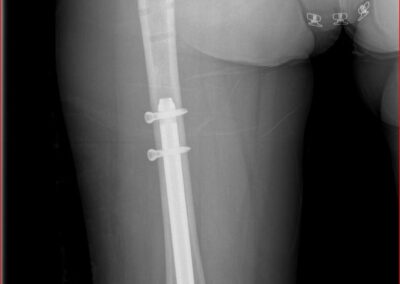

arthritis deformity surgery endoprosthesis hip prosthesis ilizarov ilizarov surgery infected nonunion knee prosthesis lengthening surgery limb lengthening surgery nonunion periprosthetic infection psodoartroz revision surgery total hip prosthesis total knee prosthesis